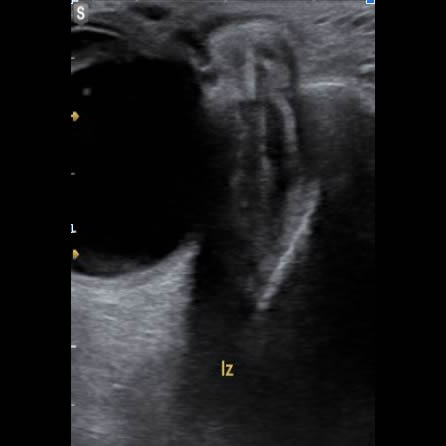

Edema palpebral de ojo izquierdo